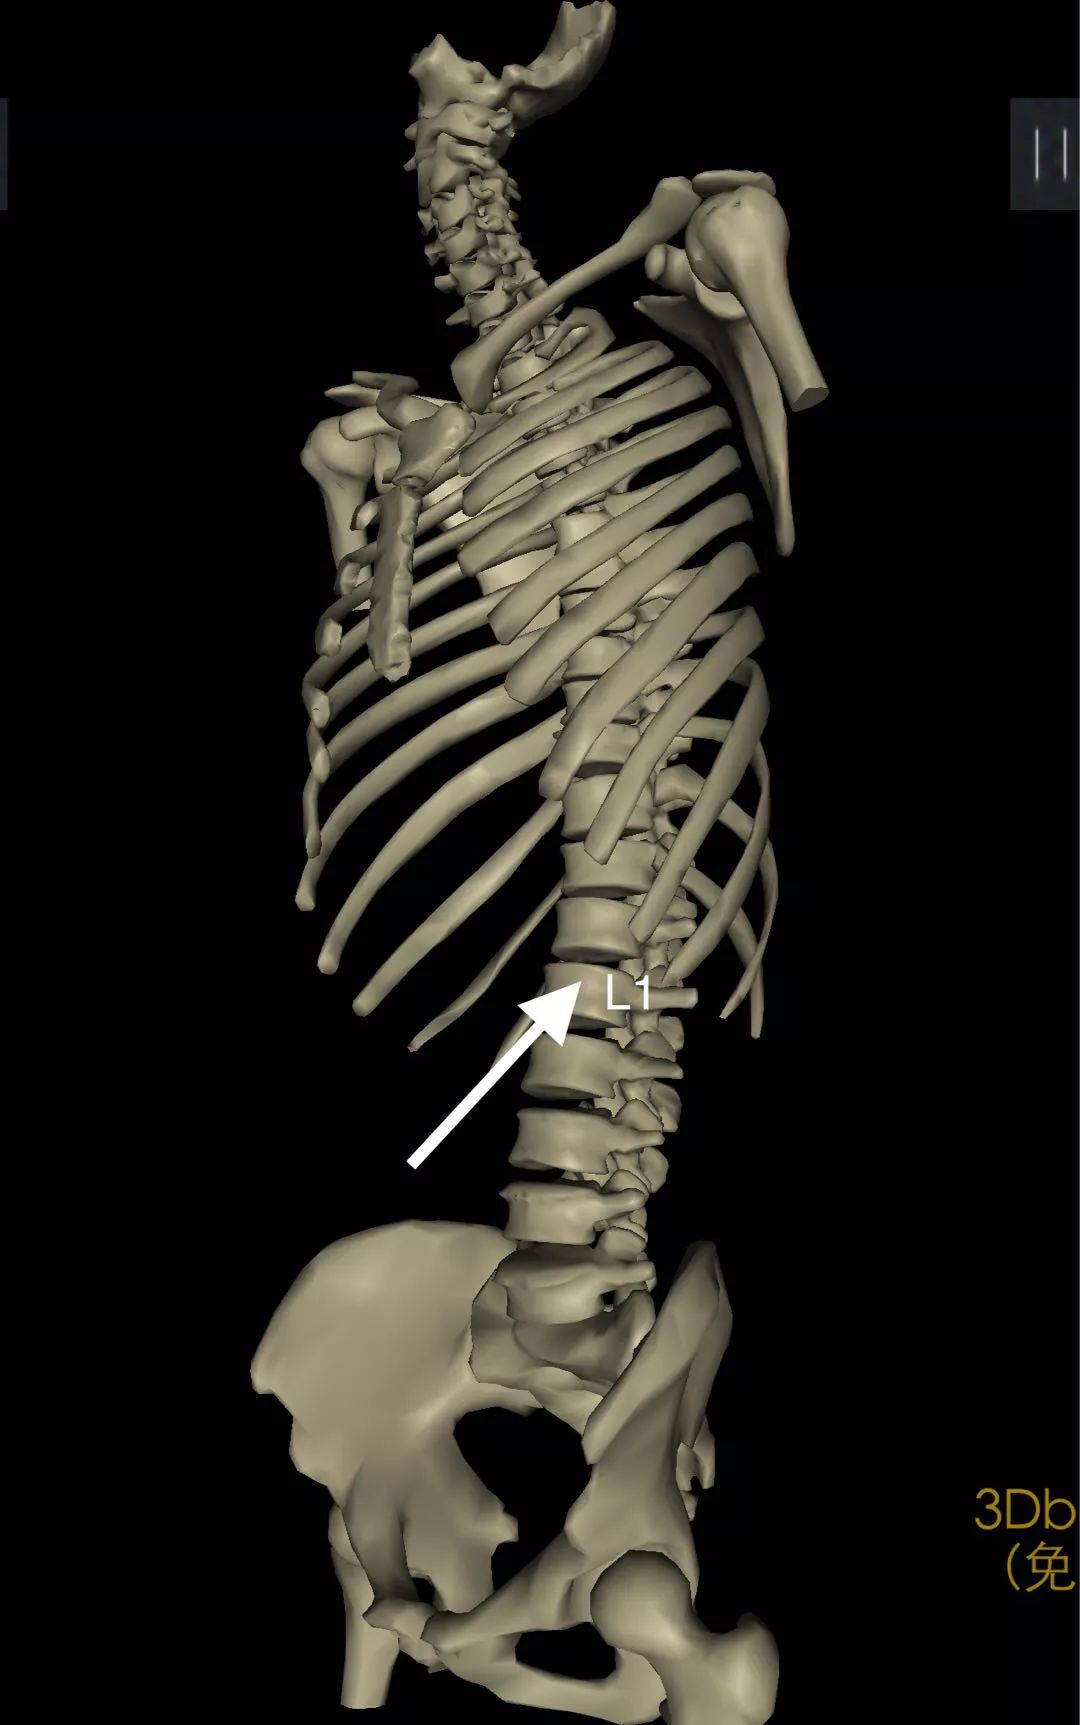

相关解剖结构

本例患者入院主因L1病变,但相邻的T12、L2椎体既往都存在压缩性骨折。T12、L1、L2椎体压缩后,脊柱的生理架构和曲线被破坏,椎间盘髓核向后方挤压椎间孔神经血管。尤其是,给L1椎体供血的肋间动脉后侧支,也被受到压迫,使得椎体出现逐渐缺血性坏死。在外力的作用下,如搬重物,或不慎扭伤时,出现L1椎体新的压缩和相应临床表现。